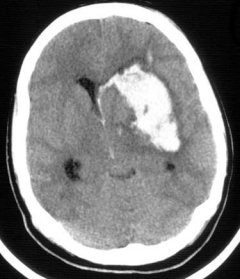

・脳内血腫:非外傷性であれば高血圧の高齢者にしばしば起こり、部位としては大脳基底核でのものが多い。また、出血が脳室内へと起こっていることもあるので頭部CTを見るときは確認するべきポイントである。

脳内血腫のCThttps://www.uic.edu/com/ferne/pdf/acep_2005_peds/perron_ich_acep_2005_peds_course.pdf

・脳室内出血:外傷によるものやクモ膜下出血、脳内出血が脳室内への穿孔に続発する場合などがある。

脳室内出血のCThttps://www.uic.edu/com/ferne/pdf/acep_2005_peds/perron_ich_acep_2005_peds_course.pdf